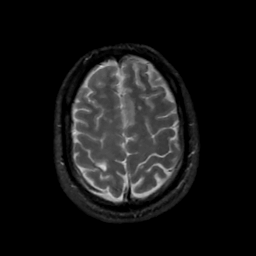

MR Study #14, June 2, 1991 -- Slice #40

[Home][Help][Clinical][Tour 1][Tour 2] Slice 40